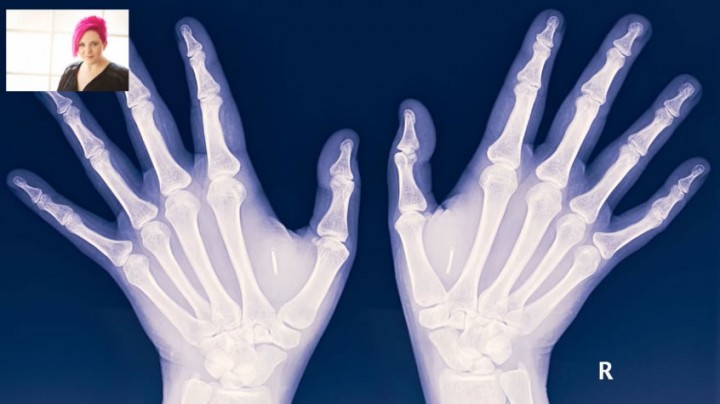

Está a crescer a moda ‘Biohacking’ em várias regiões do mundo. As pessoas sujeitam-se a implantar chips NFC e RFID no corpo para activar funcionalidades em certos dispositivos. Dizem que lhes facilita a vida...